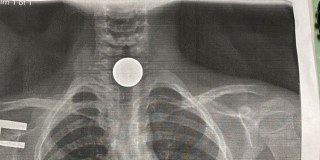

3 фото